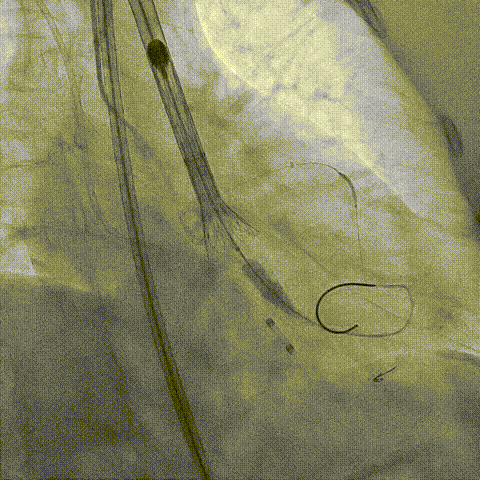

第一次释放

再次评估左冠开口,考虑调整瓣膜深度

回收后调整深度,再次释放

评估左冠开口

左冠开口切线位造影

决定左冠烟囱支架保护冠脉

调整支架位置

释放冠脉支架

释放瓣膜

造影评估

支架内后扩张

冠脉造影

根部造影

最终结果